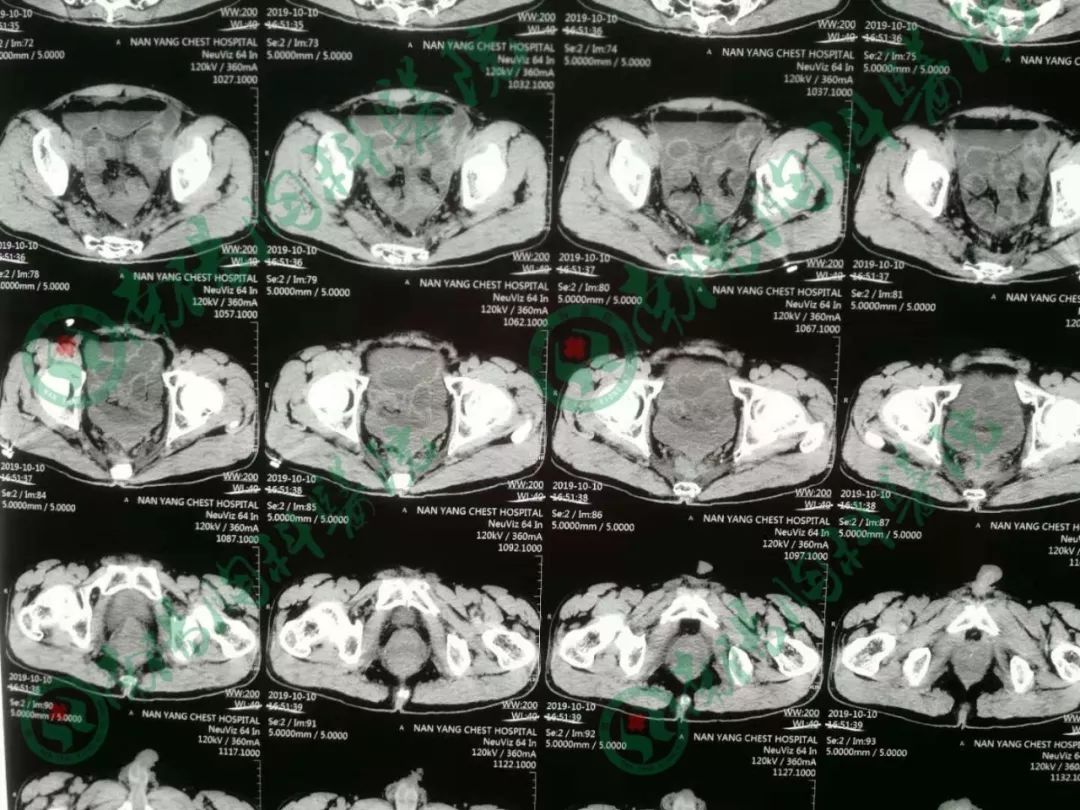

患者经过立位DR和CT检查均提示肠管高度扩张,多发阶梯状液平,病情非常棘手。

告知急诊手术,术中探查见小肠高度扩张,末段回肠扭转粘连于盆底骶前,放射性肠炎改变,呈冻结状,部分肠管受压坏死,行末段冻结扭转回肠切除术,小肠造瘘术,术后病人生命体征平稳,安返ICU。